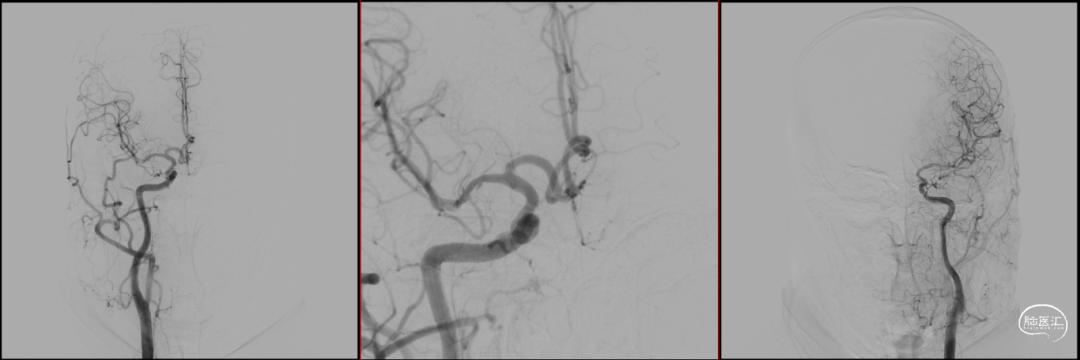

CTA:右侧颈内动脉C6段动脉瘤。

DSA:DSA提示右侧颈内动脉C6段可见多发动脉瘤。

其他血管造影未见明显异常。

术前诊断:右侧颈内动脉C6段多发动脉瘤。

DSA:DSA提示右侧大脑中动脉M1段动脉瘤,左侧大脑前动脉A1段发育不良。

术前诊断:动脉瘤位于M1主干,考虑夹层动脉瘤可能大。